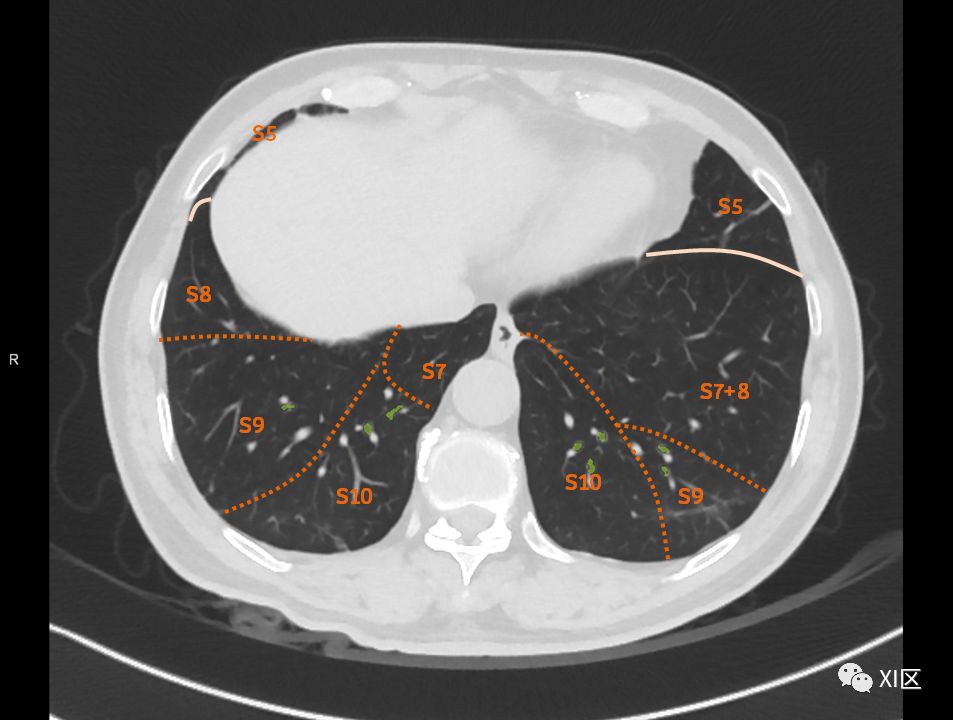

肺的断层分段示意图

在进行肺的分段时,可以上下观察浏览,沿着相应气管的走形可以更容易准确地进行分段。